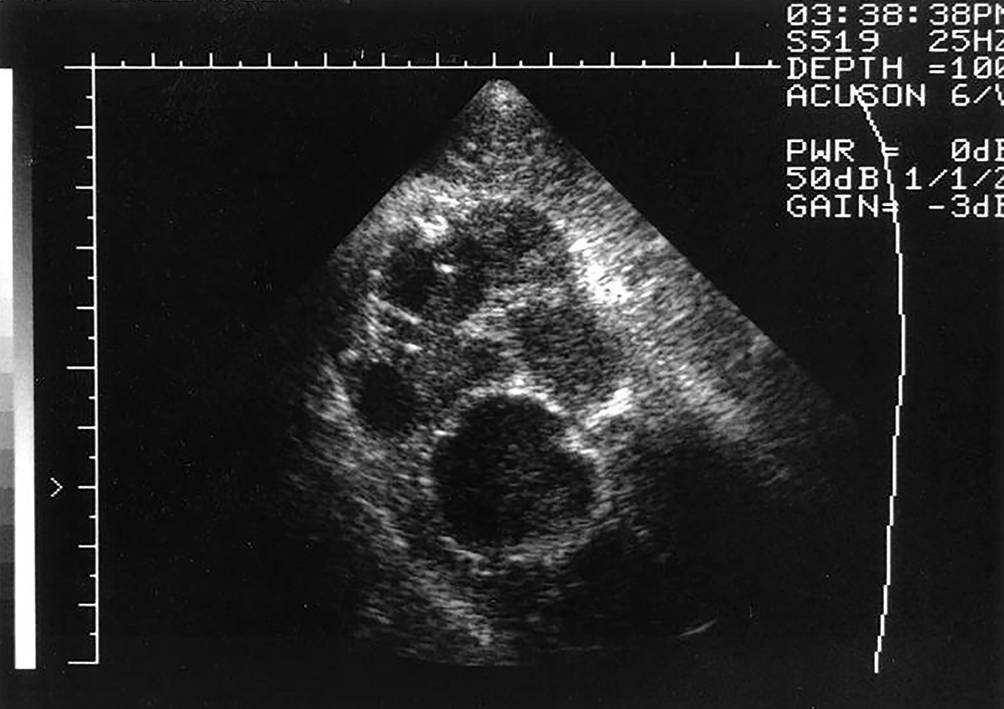

Xanthogranulomatöse Pyelonephritis ist eine selten vorkommende Form der Pyelonephritis, die bei rezidivierenden Infektionen und chronischer Obstruktion auftreten kann, wobei auch Diabetes mellitus und Fettstoffwechselstörungen als Risikofaktoren gelten. Die genaue Pathophysiologie ist aktuell noch nicht geklärt. Man geht davon aus, dass chronische Obstruktion und Entzündung die Proliferation von lipidhaltigen Makrophagen provozieren, die zu Eiterbildung und Zerstörung des Nierenparenchyms führen. Diese Theorie wird durch die Beobachtung gestützt, dass bei 2/3 der XGP-Patienten Harnsteine vorhanden sind. Das klinische Erscheinungsbild ist unspezifisch, wobei als Leitsymptome Fieber, Gewichtsverlust und Speicher- und Entleerungssymptome des unteren Harntraktes („lower urinary tract symptoms“ [LUTS]) gelten. Bei der Ultraschalluntersuchung zeigt sich ein vergrösserter und verzerrter Nierenumriss mit Verlust der normalen Nierenarchitektur und i. d. R. einem zentral gelegenen schattenbildenden Konkrement (s. Bild 4; Abb. 1).

Abb. 1

Xanthogranulomatöse Pyelonephritis: verzerrter Nierenumriss mit Verlust der normalen Nierenarchitektur und schattenbildendem Konkrement. (Mit Genehmigung aus [15]. © 1997 Elsevier Science Ireland Ltd. „All rights reserved“)